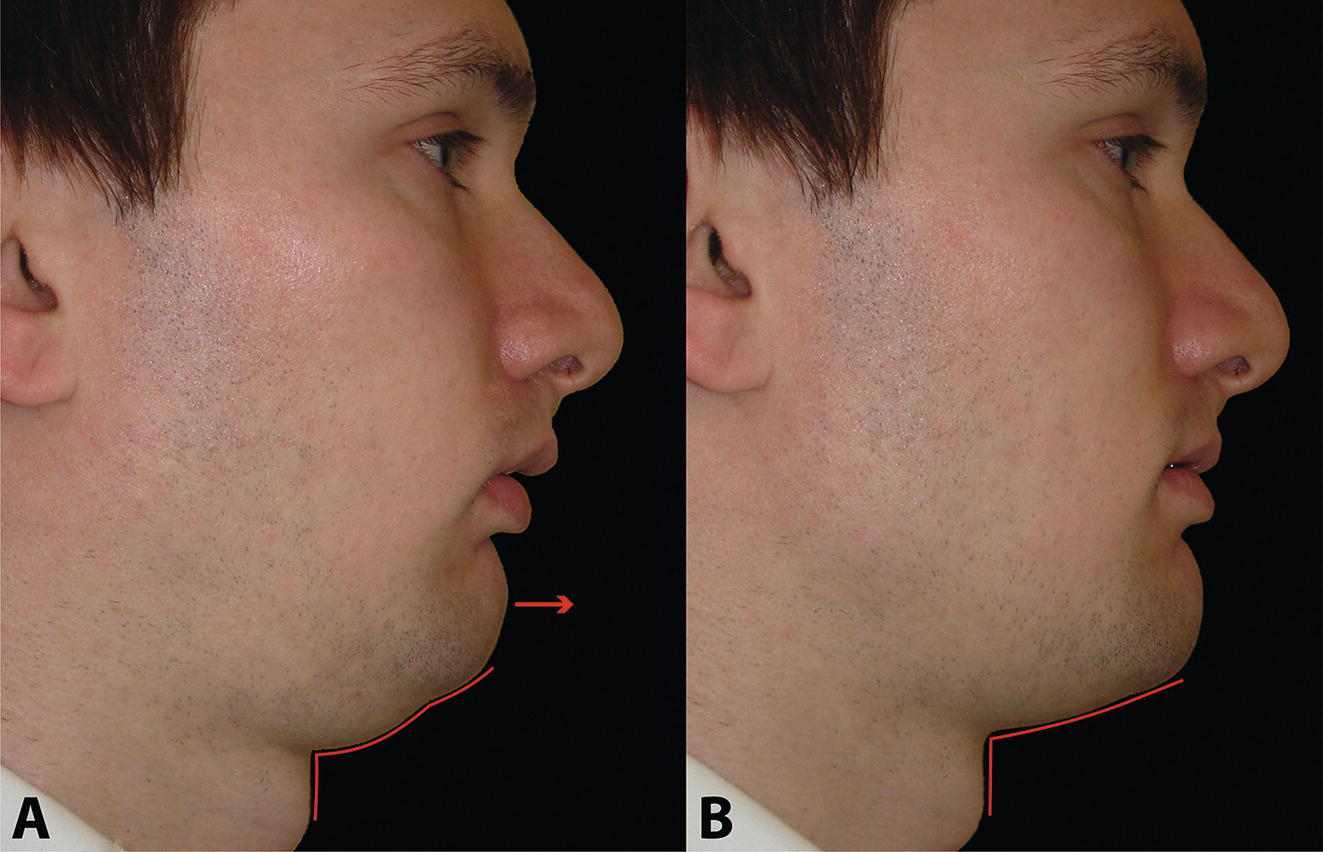

The morphology of the upper aspect of the neck and its transition with the submental region has a major impact on the aesthetics of the lower face. The anterior part of the neck extends no higher than the inferior border of the mandible. The hyoid bone is connected to the mandible by a thin sheet of muscle, the mylohyoids, which form the upper limit of the anterior part of the neck and separate the mouth from the neck. Superficially (i.e. below the mylohyoids) lies the anterior belly of digastric, while lying above it, half hidden under the mandible in the submandibular fossa, is the submandibular salivary gland (Figure 21.1). These structures are covered in by the investing layer of deep cervical fascia, which is attached to the hyoid bone and the inferior border of the mandible. The platysma muscle lies in the subcutaneous tissues. It forms a broad, flat sheet, extending from the deep fascia over the upper part of pectoralis major and the most anterior part of deltoid to the inferior border of the mandible, with some fibres reaching the lateral part of the lower lip. The sternocleidomastoid muscle forms a prominent neck landmark and may be made to stand out by turning the head towards the opposite side against resistance. The two heads of origin are from the sternum and medial one‐third of the clavicle; its attachment is to the mastoid process, which forms a readily visible and palpable bony landmark behind the lobe of the ear (Figure 21.2). Figure 21.1 Submental anatomy in relation to the mandible, with muscle attachments: Despite its importance in facial aesthetics, there is much confusion in terminology relating to the description and analysis of the submental‐cervical region. For example, the cervicomental angle has been described by perhaps half a dozen different methods, depending on the describing authority. Appropriate terminology is essential for the evaluation and accurate description of submental‐cervical aesthetics (Figure 21.3). Figure 21.2 Profile view of the face and neck with superimposed bony and muscular outlines: Cervical point (C‐point or ‘point C’): The innermost (posterior‐superior) point between the submental plane and the anterior aspect of the neck in the midsagittal plane, located at the intersection of lines drawn tangent to the submental region and the anterior neck. Submental plane: A plane or line constructed between the cervical point (C‐point) and the most inferior point on the chin (soft tissue menton, Me’). If C‐point cannot be defined, the submental plane is drawn tangent to the submental contour passing through soft tissue menton. The submental plane is referred to as the ‘throat’ plane by some authorities; the submental length (distance from C‐point to menton) is therefore sometimes referred to as the ‘throat length’. Cervical plane: A plane or line drawn tangent to the anterior soft tissue contour of the neck above and below the thyroid prominence. Figure 21.3 Submental plane, cervical plane and cervical point (C‐point). A thorough understanding of the aetiological factors involved in creating a poor aesthetic contour of the submental‐cervical region is required in order to diagnose and appropriately plan the correction of the aesthetic submental‐cervical angles and contour. The tonicity of the submental‐cervical skin, the muscular support of the neck, the isolated fatty deposits in the submental‐cervical region, the skeletal framework of the mandible and chin, and the spatial position of the hyoid bone are all important parameters in the aesthetic analysis of the submental‐cervical region. An undesirable submental‐cervical contour may result from: It is paramount that the clinical evaluation is undertaken with the patient in natural head position (NHP). Even a small degree of upward or downward tilting of the head must be avoided as it may have a profound effect on the contour of the submental‐cervical region. A number of parameters may be analysed in the clinical evaluation of the submental‐cervical region: Mandibular and/or chin deficiency in the sagittal plane, and/or posterior (downward and backward) rotation of the mandible, often secondary to vertical maxillary excess, may contribute to the undesirable aesthetic appearance of the submental‐cervical region (Figure 21.4). It is helpful to have the ‘Class II skeletal pattern’ patient posture the mandible forward to a more normal sagittal position, which will concurrently stretch the submental soft tissues. If this manoeuvre improves the submental‐cervical aesthetics visually, and tightens the submental soft tissues to palpation, then correction of the underlying skeletal discrepancy is likely to improve the submental‐cervical aesthetics (Figure 21.5). Figure 21.4 Class II jaw relationship due to mandibular deficiency and significant compensatory proclination of the mandibular incisor teeth; the submental‐cervical angle is increased. Figure 21.5 (A) Patient with Class II jaw relationship due to mandibular deficiency. (B) Posturing the mandible forward to a more normal sagittal position will concurrently stretch the submental soft tissues. Figure 21.6 Skin laxity test. The converse is also true. Surgical procedures to set back the mandible, or set down the maxilla causing posterior mandibular rotation, will tend to have undesirable consequences on submental‐cervical aesthetics (see Figure 19.22). The patient must be informed of these potential untoward consequences of orthognathic surgery, and should be advised of the possible future need for aesthetic surgical procedures of the submental‐cervical region. The laxity of the submental‐cervical skin may be evaluated by the skin laxity test: the clinician stands behind the patient and gently pulls the soft tissues upward and backward just inferior and anterior to the ear, simulating a neck lift (Figure 21.6). If the soft tissues are easily displaced upward there is increased laxity of the skin, termed redundant skin.1 If following this manoeuvre there is still submental fullness, the patient has redundant skin and excessive submental‐cervical adiposity. Reduced tonicity of the platysma may contribute significantly to submental fullness.2,3 In addition, the platysma muscle may or may not merge anatomically across the midline. Frequently, excessive submental fullness results not only from redundant skin but from the redundant medial borders of the platysma muscle that fail to meet in the midline. Increased submental‐cervical fat accumulation may be independent of generalized body fat; in some patients subcutaneous fat accumulation in this region may remain despite extensive weight loss. In younger patients the fat usually accumulates between the skin and the platysma muscle. In older patients, the fat may accumulate both deep and superficial to the platysma (Figure 21.9). The quantity of submental fat may be estimated by the submental pinch test: the submental soft tissues are gently gripped between the thumb and index finger.1 This manoeuvre should be performed with the patient both in NHP and with the head extended and contracting the platysma muscle; in this way the clinician may determine whether the submental fat is predominantly supraplatysmal or subplatysmal. Figure 21.7 Platysma view: With the head tilted slightly back in frontal view, grimacing and clenching the teeth will induce contraction of the platysma muscle. The muscular fascicles of the platysma become visible beneath the skin. Figure 21.8 Platysmal bands may be evident in repose in an ageing neck. Figure 21.9 Submental adiposity. Figure 21.10 The definition of the inferior border of the mandible is an important aesthetic parameter as it defines the demarcation between the face and neck. (Detail, Woman’s Head, Leonardo da Vinci, c. 1470–76, Galleria degli Uffizi, Florence.) The definition of the inferior border of the mandible, from the chin to the gonial angle, is an important aesthetic parameter, as it defines the demarcation between the face and neck (Figure 21.10). In frontal view, the transition from the upper aspect of the neck to the inferior border of the mandible has a subtle hourglass appearance, with its superior aspect being well defined by the concavity immediately below the inferior mandibular borders (Figure 21.11).1 The soft tissues of the neck normally closely adhere to the structures underlying them. Lack of definition of the inferior mandibular border may be due to increased soft tissue laxity, fat accumulation, mandibular/chin deficiency or hyoid bone sag. Figure 21.11 In frontal view, the transition from the upper aspect of the neck to the inferior border of the mandible has a subtle hourglass appearance. The submandibular salivary gland envelopes the posterior border of the mylohyoid muscle, half hidden in the submandibular fossa on the medial aspect of the mandible (see Figure 21.1). Submandibular fullness may result from an increase in size of the submandibular gland, laxity of the neck fascial layer or submandibular gland ptosis. Rhytidectomy and platysma plication address this problem indirectly by increasing the fascial support for the gland. However, patients may develop a more noticeable submandibular fullness as the removal of submental fat unmasks the ptotic gland. Partial or complete submandibular gland resection provides definite improvement of submandibular fullness resulting from glandular hypertrophy or ptosis, but may be considered too radical for a patient with a normal‐sized, ptotic submandibular gland. Guyuron et al.4 have described the basket submandibular gland suspension technique, directly supporting the gland onto the inner aspect of the inferior surface of the mandible with a strong piece of fascia. This technique helps eliminate submandibular fullness in patients with normal‐sized, ptotic glands. Resection remains the treatment of choice for the correction of glandular hypertrophy. Figure 21.12 Of the ‘six visual criteria’ of the profile view for ‘success in restoring the youthful neck’, the following are demonstrated: 1 Distinct inferior mandibular border 4 Visible anterior border of sternocleidomastoid muscle 5 Submental‐cervical (submental‐neck) angle between 105° and 120° 6 Sternocleidomastoid‐submental plane (SM‐SM) angle approximately 90°